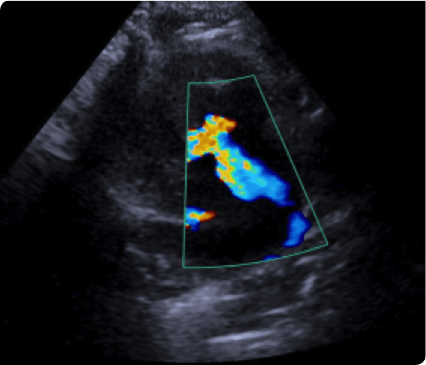

소형견에서 가장 많이 발생하는 이첨판폐쇄부전증(MMVD)과 고양이에서 가장 많이 발생하는 비대성심근병증(HCM)의

일산시티동물의료센터는 최신 고해상도 초음파 장비를 통해 세밀하게 심장을 정밀하게 분석하여 심장질환을 진단합니다.